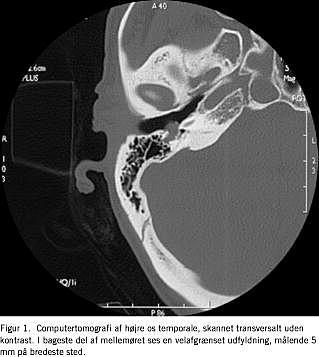

Ved computertomografi (CT) af højre os temporale, skannet transverselt uden kontrast, sås en relativt velafgrænset, ikkedestruktiv udfyldning (Figur 1 ).

Ud fra CT'en kunne det ikke afgøres, om det var en glomustumor eller et FS.